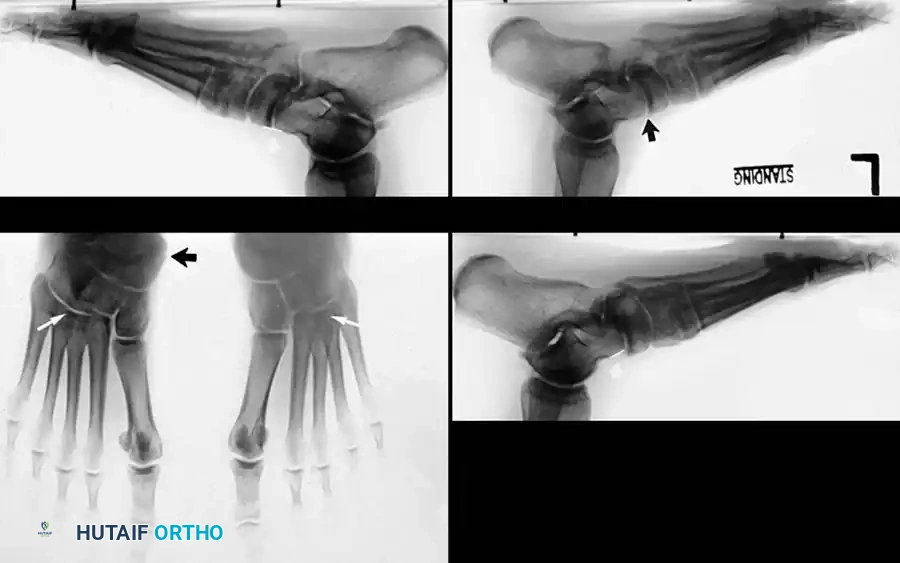

Clinical Pearl: The loss of the medial longitudinal arch can occur at the talonavicular, navicular-cuneiform, or cuneiform-metatarsal articulations. A weight-bearing lateral radiograph may initially show no bony collapse, appearing identical to the asymptomatic contralateral foot, even in the presence of obvious clinical pes planus.

- Clinical Findings: Loss of PTT function resulting in a flexible flatfoot deformity (hindfoot valgus, midfoot abduction). Mild lateral sinus tarsi pain may begin to manifest.

- Clinical Findings: A fixed, rigid hindfoot valgus and midfoot abduction deformity. Significant lateral sinus tarsi impingement pain is the primary complaint.

- Radiography: Degenerative arthritic changes are visible in the subtalar and/or talonavicular joints.

- Clinical Findings: Valgus tilt of the talus within the ankle mortise. The deformity involves not just the hindfoot, but the tibiotalar joint itself.

2. Medial Displacement Calcaneal Osteotomy (MDCO):

To correct hindfoot valgus and shift the mechanical axis medially, reducing strain on the FDL transfer.

* The posterior tuberosity is translated medially by 10 to 15 mm.

Indicated if severe midfoot abduction is present (uncovering of the talar head > 40%).